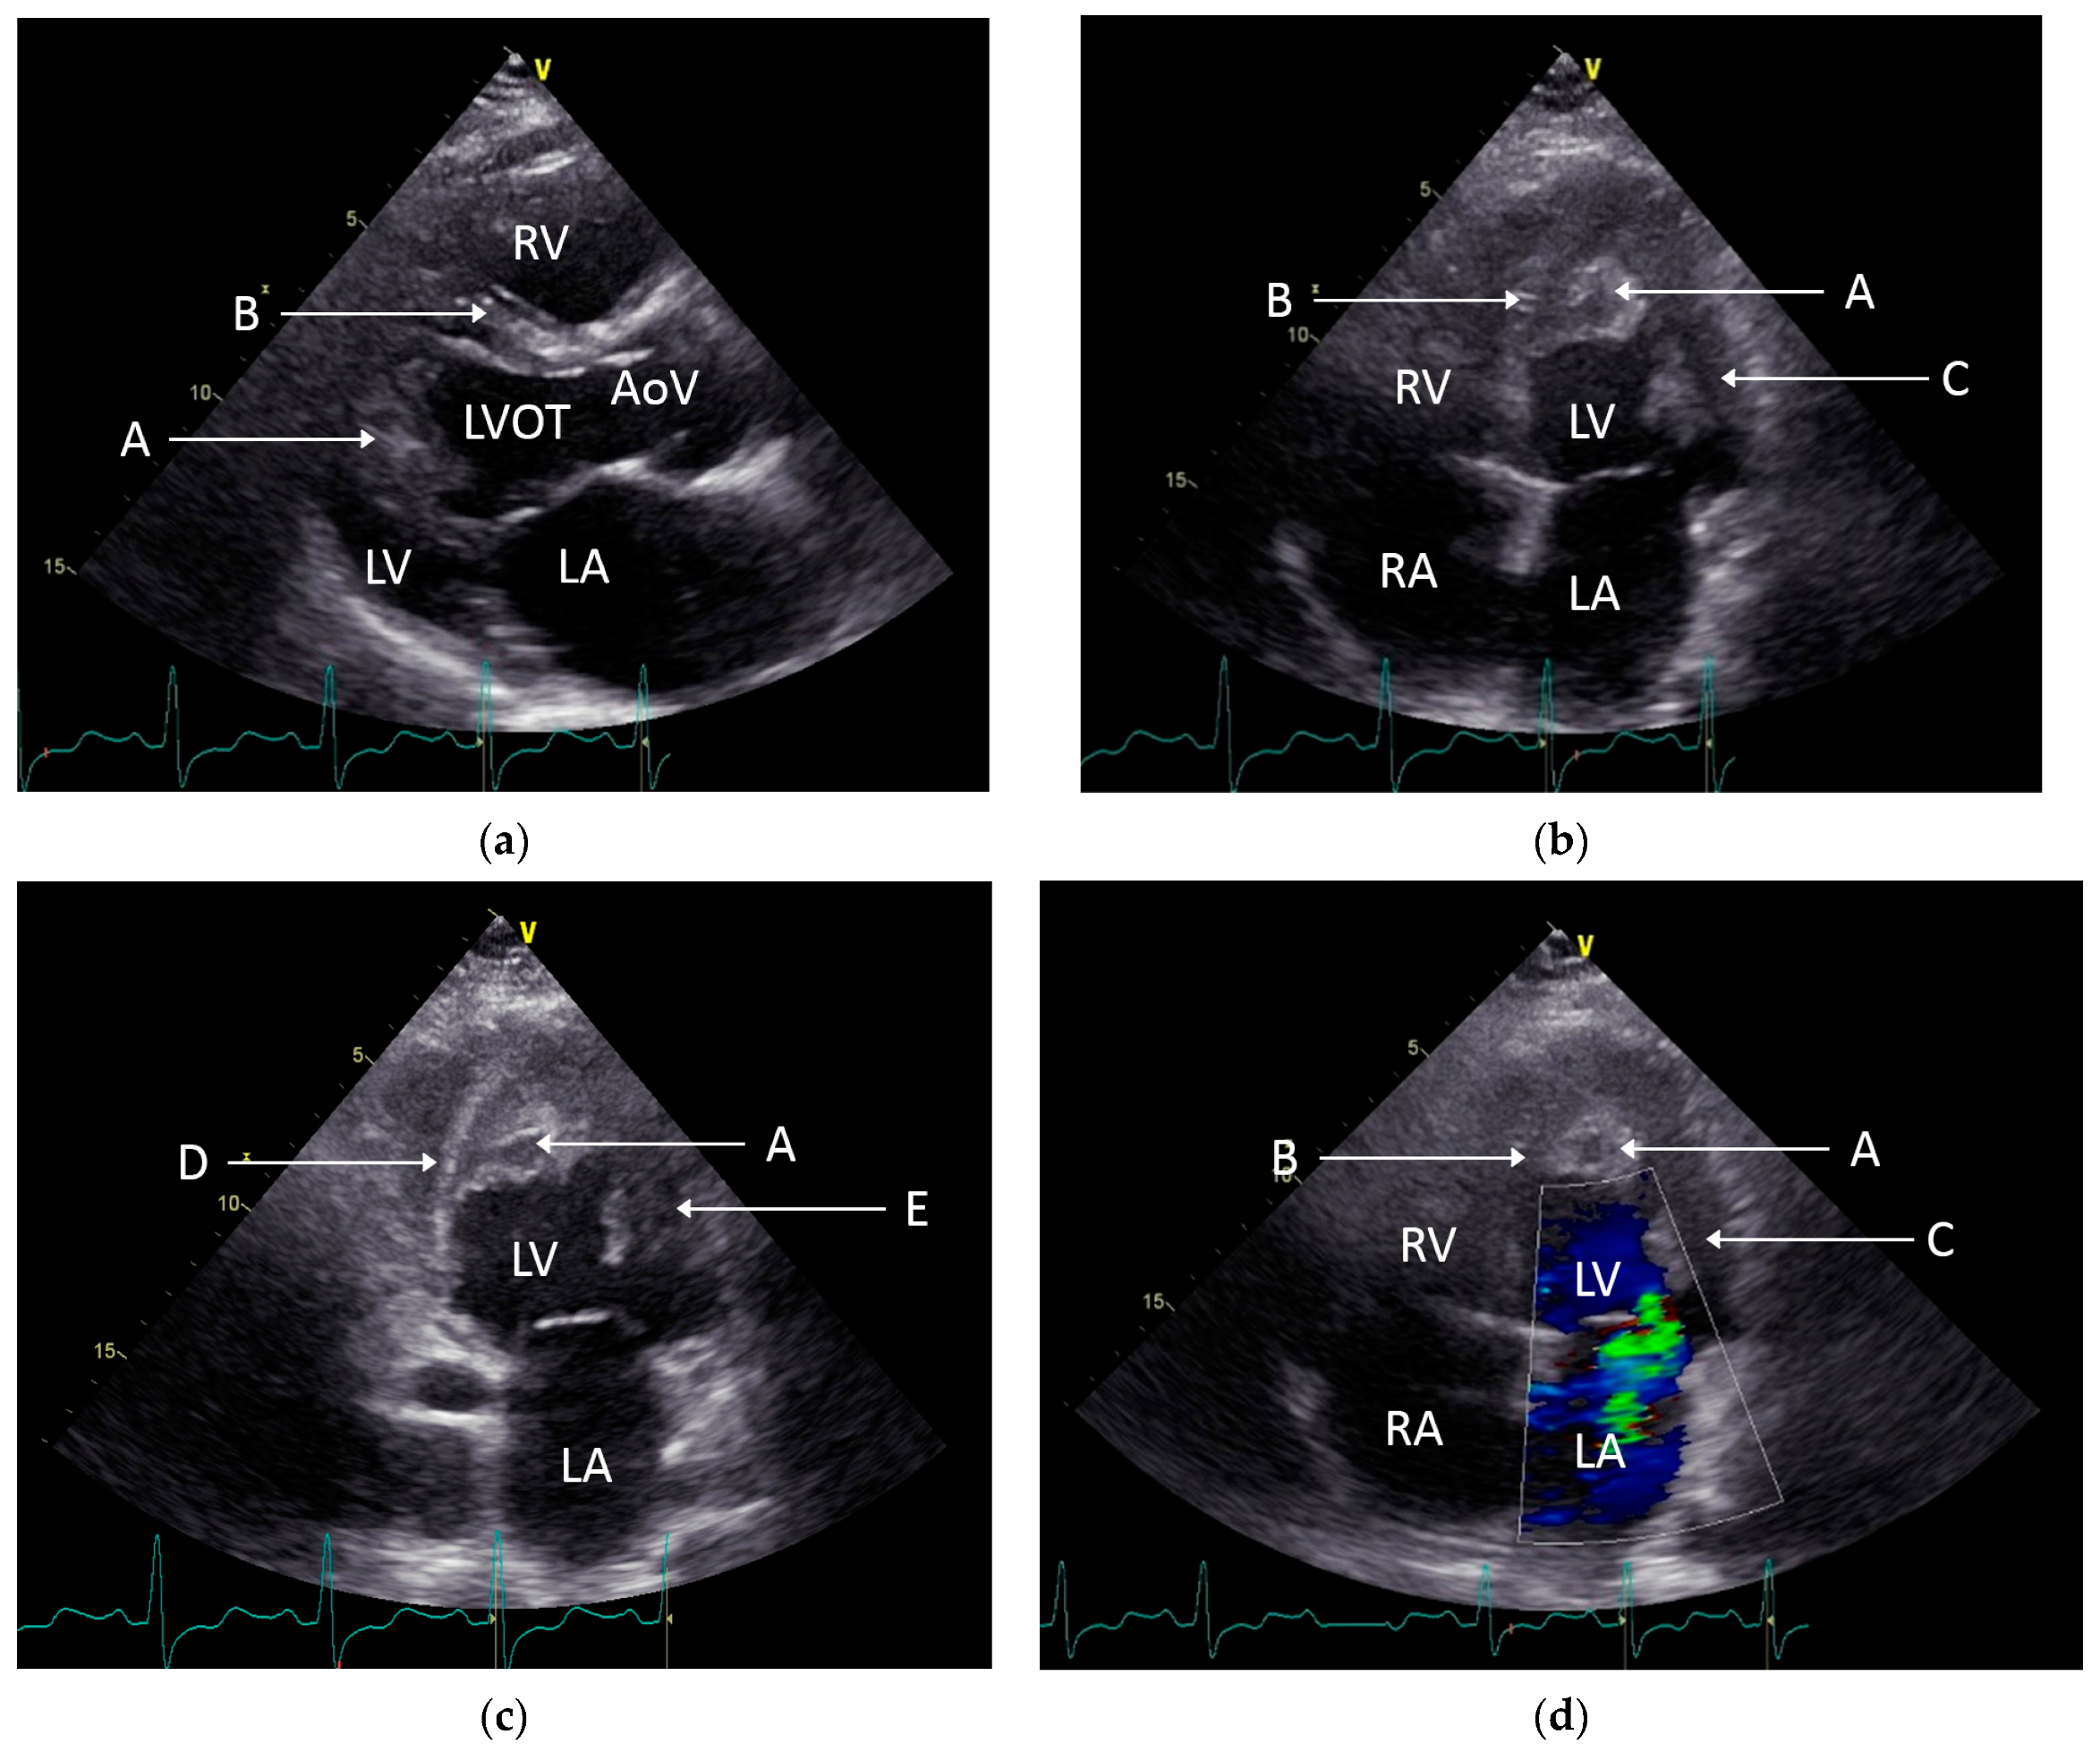

2. Case Presentation

3. Discussion